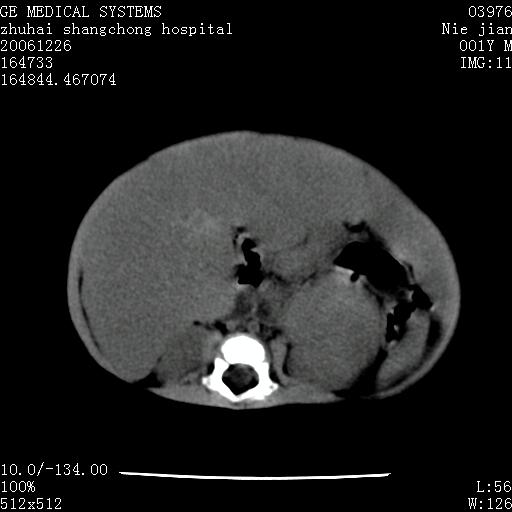

3个月婴儿腹胀来看。

【临床特点】

婴儿,腹胀,无特殊症状,未提供详细资料。

【影像特征】

1、肝明显增大,肝弥漫性低密度灶。

2、肾上腺区见类圆形肿块,其内密度不均,见片状偏高密度。

【诊断】

1、肝弥漫性病变,考虑急性肝炎致广泛脂肪浸润可能性大。

2、肾上腺区占位,假性肿瘤?肾上腺血肿(感染所致)?

一年后

1、肝硬化,脂肪浸润消失。

2、假性肿瘤消失或血肿吸收。

【分析】

1、关键着眼点:肝脏弥漫性病变内有没有走形的血管,仔细看部分低密度内有血管影(要有增强扫描作为证据就好了),说明并非肿瘤样病变,而是脂肪浸润。即可能不是转移瘤或原发肿瘤,低密度的形态上看,是片状,也不像肿瘤。

2、儿童肝炎最常见的是感染,有时食入性损害或药物也可致肝脏炎症,肝炎致大空泡型脂肪变性,是一种无痛性疾病,无症状,病因有营养异常、代谢性疾病、药物及病毒感染。所以脂肪变性与感染有关。

3、肝炎的结局是肝硬化,而恰恰一年后复查,已有肝硬化表现。肿瘤一般那会消失,那叫奇迹。

4、肾上腺出血也可见于败血症及感染,通常包块在数周内消失,ct表现包块内有偏高密度,可能是亚急性血肿的表现。假性肿瘤即腹部肠管积液、扩张血管及邻近结构的伪像。自然会消失。

5、因此,感染可以贯穿一切,解释一切。肿瘤自然消退?可能吗?那些应要无道理的创造奇迹的事情会那么容易发生吗?